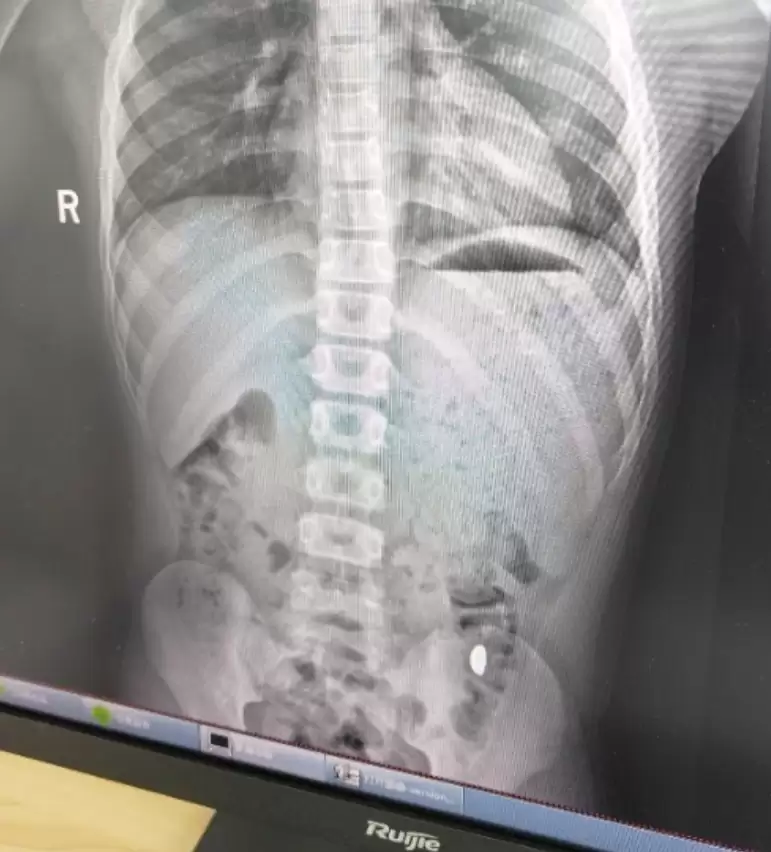

经检查发现,孩子吞下去的黄金碎片已经进入大肠,目前没有造成堵塞或划伤消化道的情况,暂时无大碍

d4.jpg

医生叮嘱刘女士,接下来几天一定要密切观察孩子的排便情况,确认碎金是否能随粪便排出,同时还要按时带孩子复查,有任何不适要立刻就医。